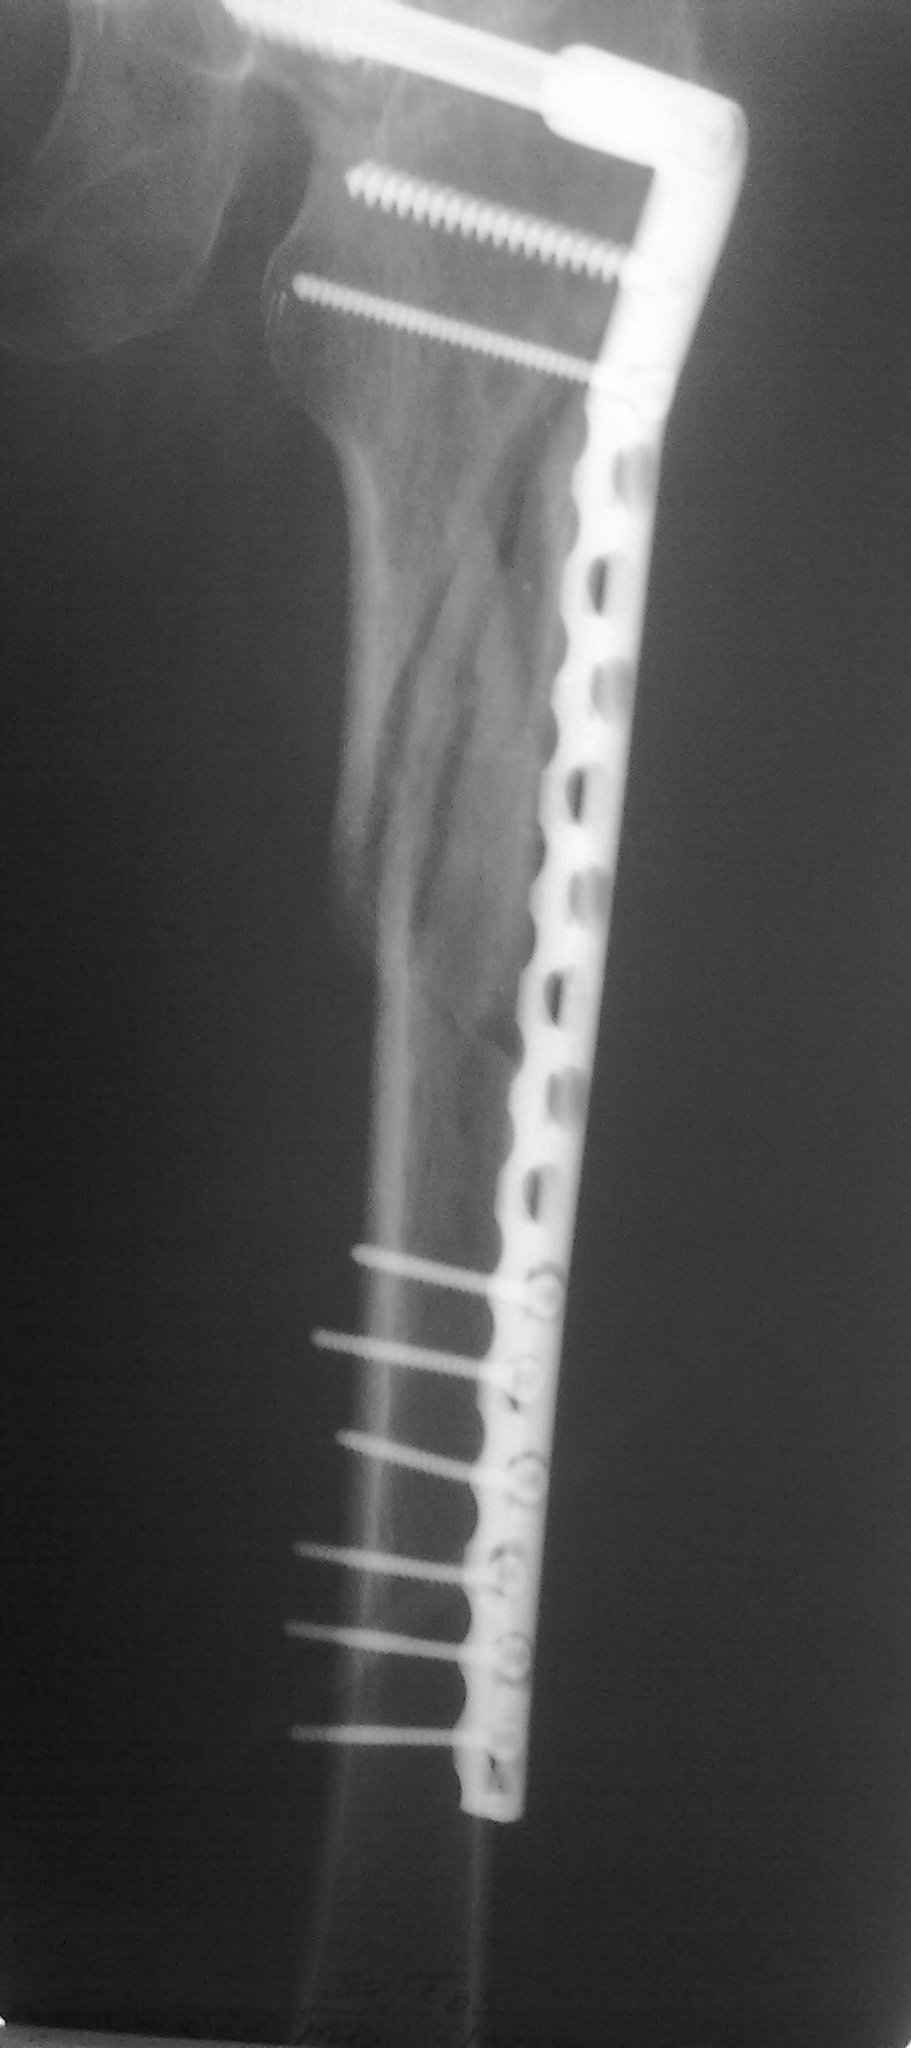

Пациент 83 года. Реконструктивный бедренный стержень Chm

А может для первого опыта подобрать и перелом и больную полегче, а в данном случае ограничиться DCS?